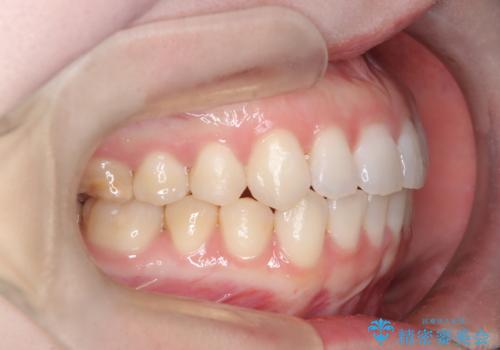

審美ワイヤー矯正とTAD併用による犬歯の遠心移動

- 歯並びの乱れを改善したいと来院されました。精密検査の結果、犬歯を奥へ動かすことで、より美しい口元と安定した咬み合わせが得られると診断。患者様のご希望から、目立ちにくい審美ワイヤー矯正を採用し、効率的な歯の移動のために**リンガルアーチとTAD(矯正用アンカースクリュー)**を併用する計画を立てました。これにより、抜歯せずにスペースを確保し、犬歯をスムーズに遠心へ移動させます。

今回の矯正では、装置が目立たないよう透明なブラケットと白いワイヤーを使用。さらに、効率的な歯の移動のために、歯の裏側にリンガルアーチを設置しました。また、確実な奥歯の移動のために**TAD(矯正用アンカースクリュー)**を一時的に使用。これにより、犬歯を狙った位置へ正確に動かすことが可能に。目立ちにくい装置で快適に過ごしながら、理想的な歯並びと咬み合わせを獲得していただけました。